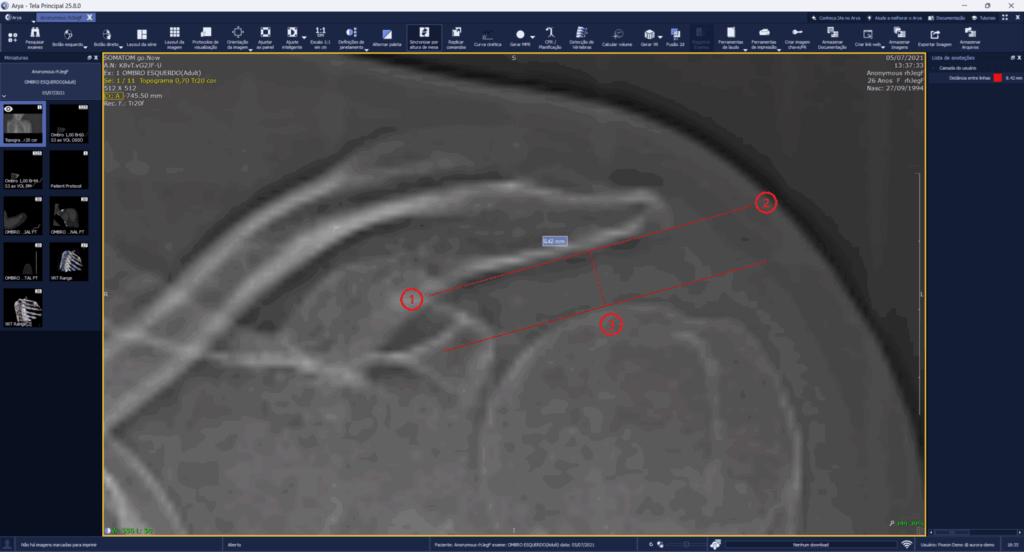

La nueva herramienta Distancia entre Líneas permite trazar dos líneas paralelas y medir el espacio entre ellas, resultando especialmente útil para verificar distancias como la acromiohumeral, acromioclavicular e intraarticular de la rodilla, entre otras.

Con el objetivo de generar mayor eficiencia en el análisis de las imágenes, el cálculo se realiza con solo tres clics: los dos primeros definen el inicio y el final de la primera línea, y el tercer clic define la posición de la segunda, registrando la distancia efectiva entre ambas.

- Nueva medición automática de la Distancia entre Líneas paralelas de dos anatomías, aportando agilidad en la evaluación de cavidades y espacios articulares.